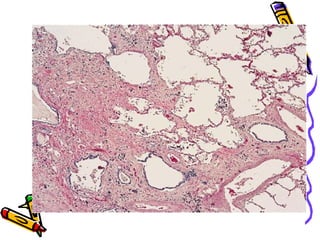

Anthracosis (urban

dwellers)

morphology

• Gross Streaks of anthracotic

pigment in lymphatics and draining

hilar lymph nodes

• Microscopy

• Carbon pigment in alveolar and

interstitial macrophages,in

connective tissue and lymphatics

• and lung hilus.

Simple CWP

Gross :Coal macules (1-2mm) & Coal

nodules >upper lobes and upper zones

of lower lobes

Microscopy: Carbon laden macrophages

& delicate collagen fibres. Adjacent

to respiratory bronchioles initially

(where dust settles), later interstium

& alveoli.

Dilatation of respiratory

bronchioles –focal dust emphysema